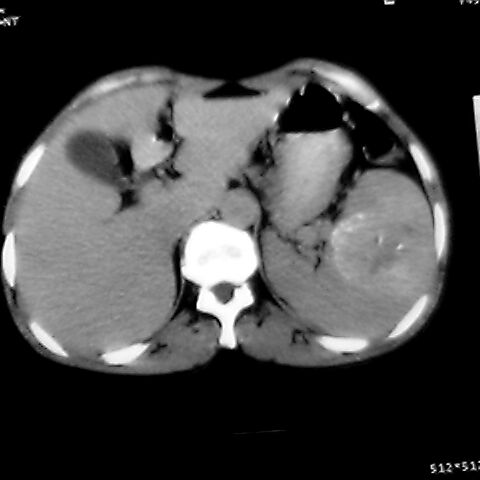

女 48岁 食道癌术前体检发现脾占位。

脾胀内部巨大低密度肿块,边界清或不清,中心坏死,轻度增强,内见散在钙化,结合食道癌病史多考虑:转移癌.

脾脏低密度灶伴钙化,增强化明显,中心见液化坏死灶,强化延时明显。考虑血管瘤。转移瘤待排。